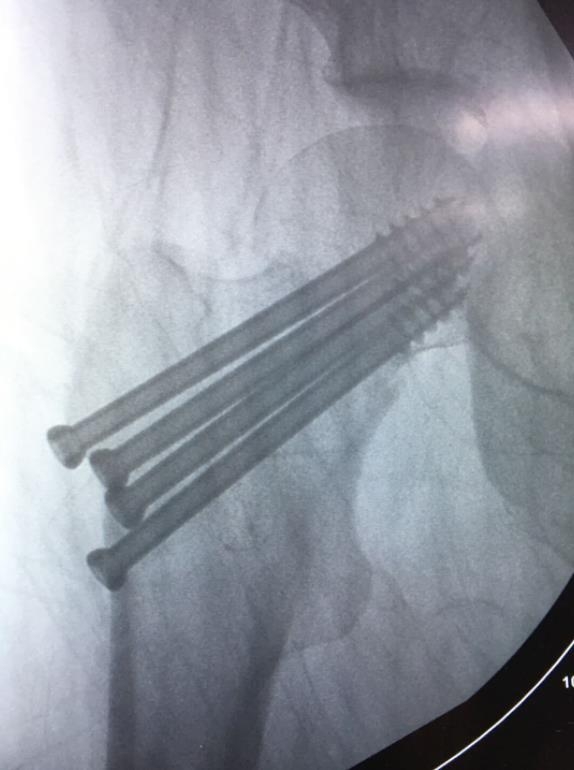

1、经皮沿股骨颈轴线置入空心钉导针,确保导针平行;

2、标准放置螺钉为倒三角形,其中下方螺钉在股骨矩,后方螺钉在后方骨皮质、研究发现倒三角形平行三枚螺钉能提供最佳的固定强度;

4、两个平面透视导针位置良好后切开皮肤,空心钻铭孔,导针引导下拧入空心钉,空心钉确保所有螺纹位于骨折线近端,螺钉头应距离软骨下骨5mm。

临床病例